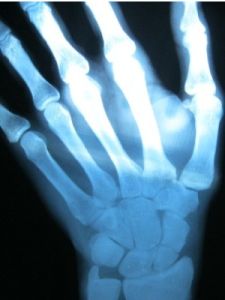

舟骨骨折類型根據X線片上所顯示骨折線的部位不同,一般分為以下3種類型。

疑有骨折者應拍攝正位、側位、舟骨位、前後和後前斜位X線片,大多數骨折可以顯示出來。不完全骨折其骨折線可能顯示不清或不顯示,容易造成漏診。對於局部症狀明顯者,應先按骨折處理,用石膏固定2周后再拍片複查,可能會因骨折處骨質吸收,能顯示出骨折線。亦可及早行CT檢查。